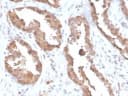

IgGApplications:

WB, IHC-PFormat: